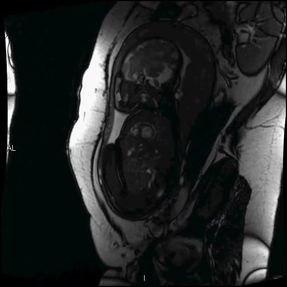

Physiological Fetal Cardiac Anatomy

Pathological Fetal CHD